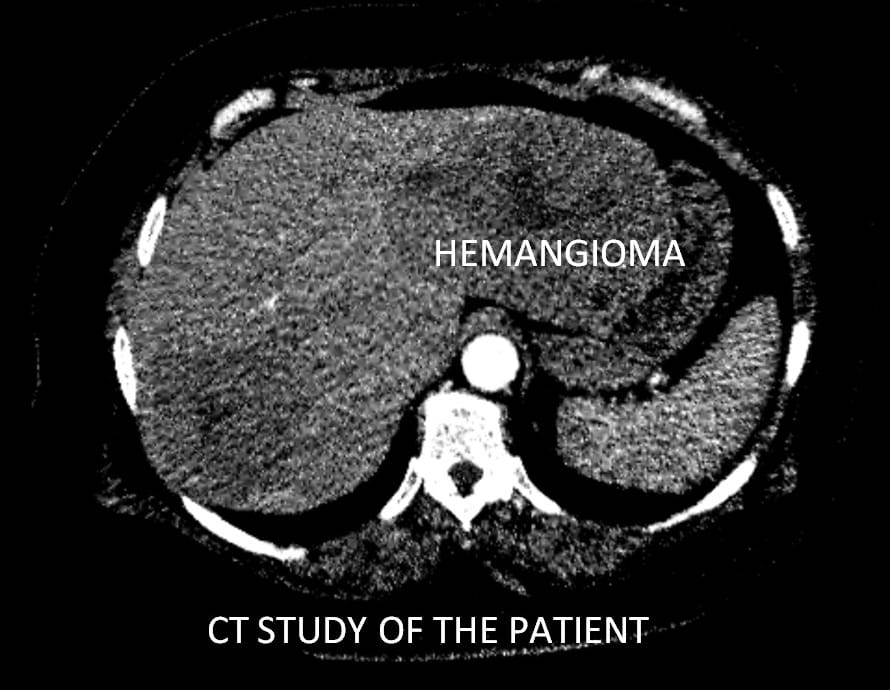

نجح الفريق الطبي بقسم الأشعة التداخليه بمستشفيات جامعة بنها، بمساعدة لواء طبيب اسامة زين أستاذ الاشعة التداخلية بالاكاديمية الطبية العسكرية، في عمل عملية حقن ورم كبدي كبير الحجم لمريضة تبلغ من العمر 51 عامًا وذلك بعد عمل أشعة مقطعية ورنين مغناطيسي لتحديد طبيعة الورم.

وتعتبر هذه العملية الأول من نوعها يتم علاجها من خلال جهاز الأشعة المقطعية ١٢٨ متعدد المقاطع حيث تم علاج الورم من خلال قسطرة بالشريان الكبدي للفص الأيسر من الكبد ونجاح عملية الحقن التي تظهر اختفاء الأوعية الدموية المغذية للورم.